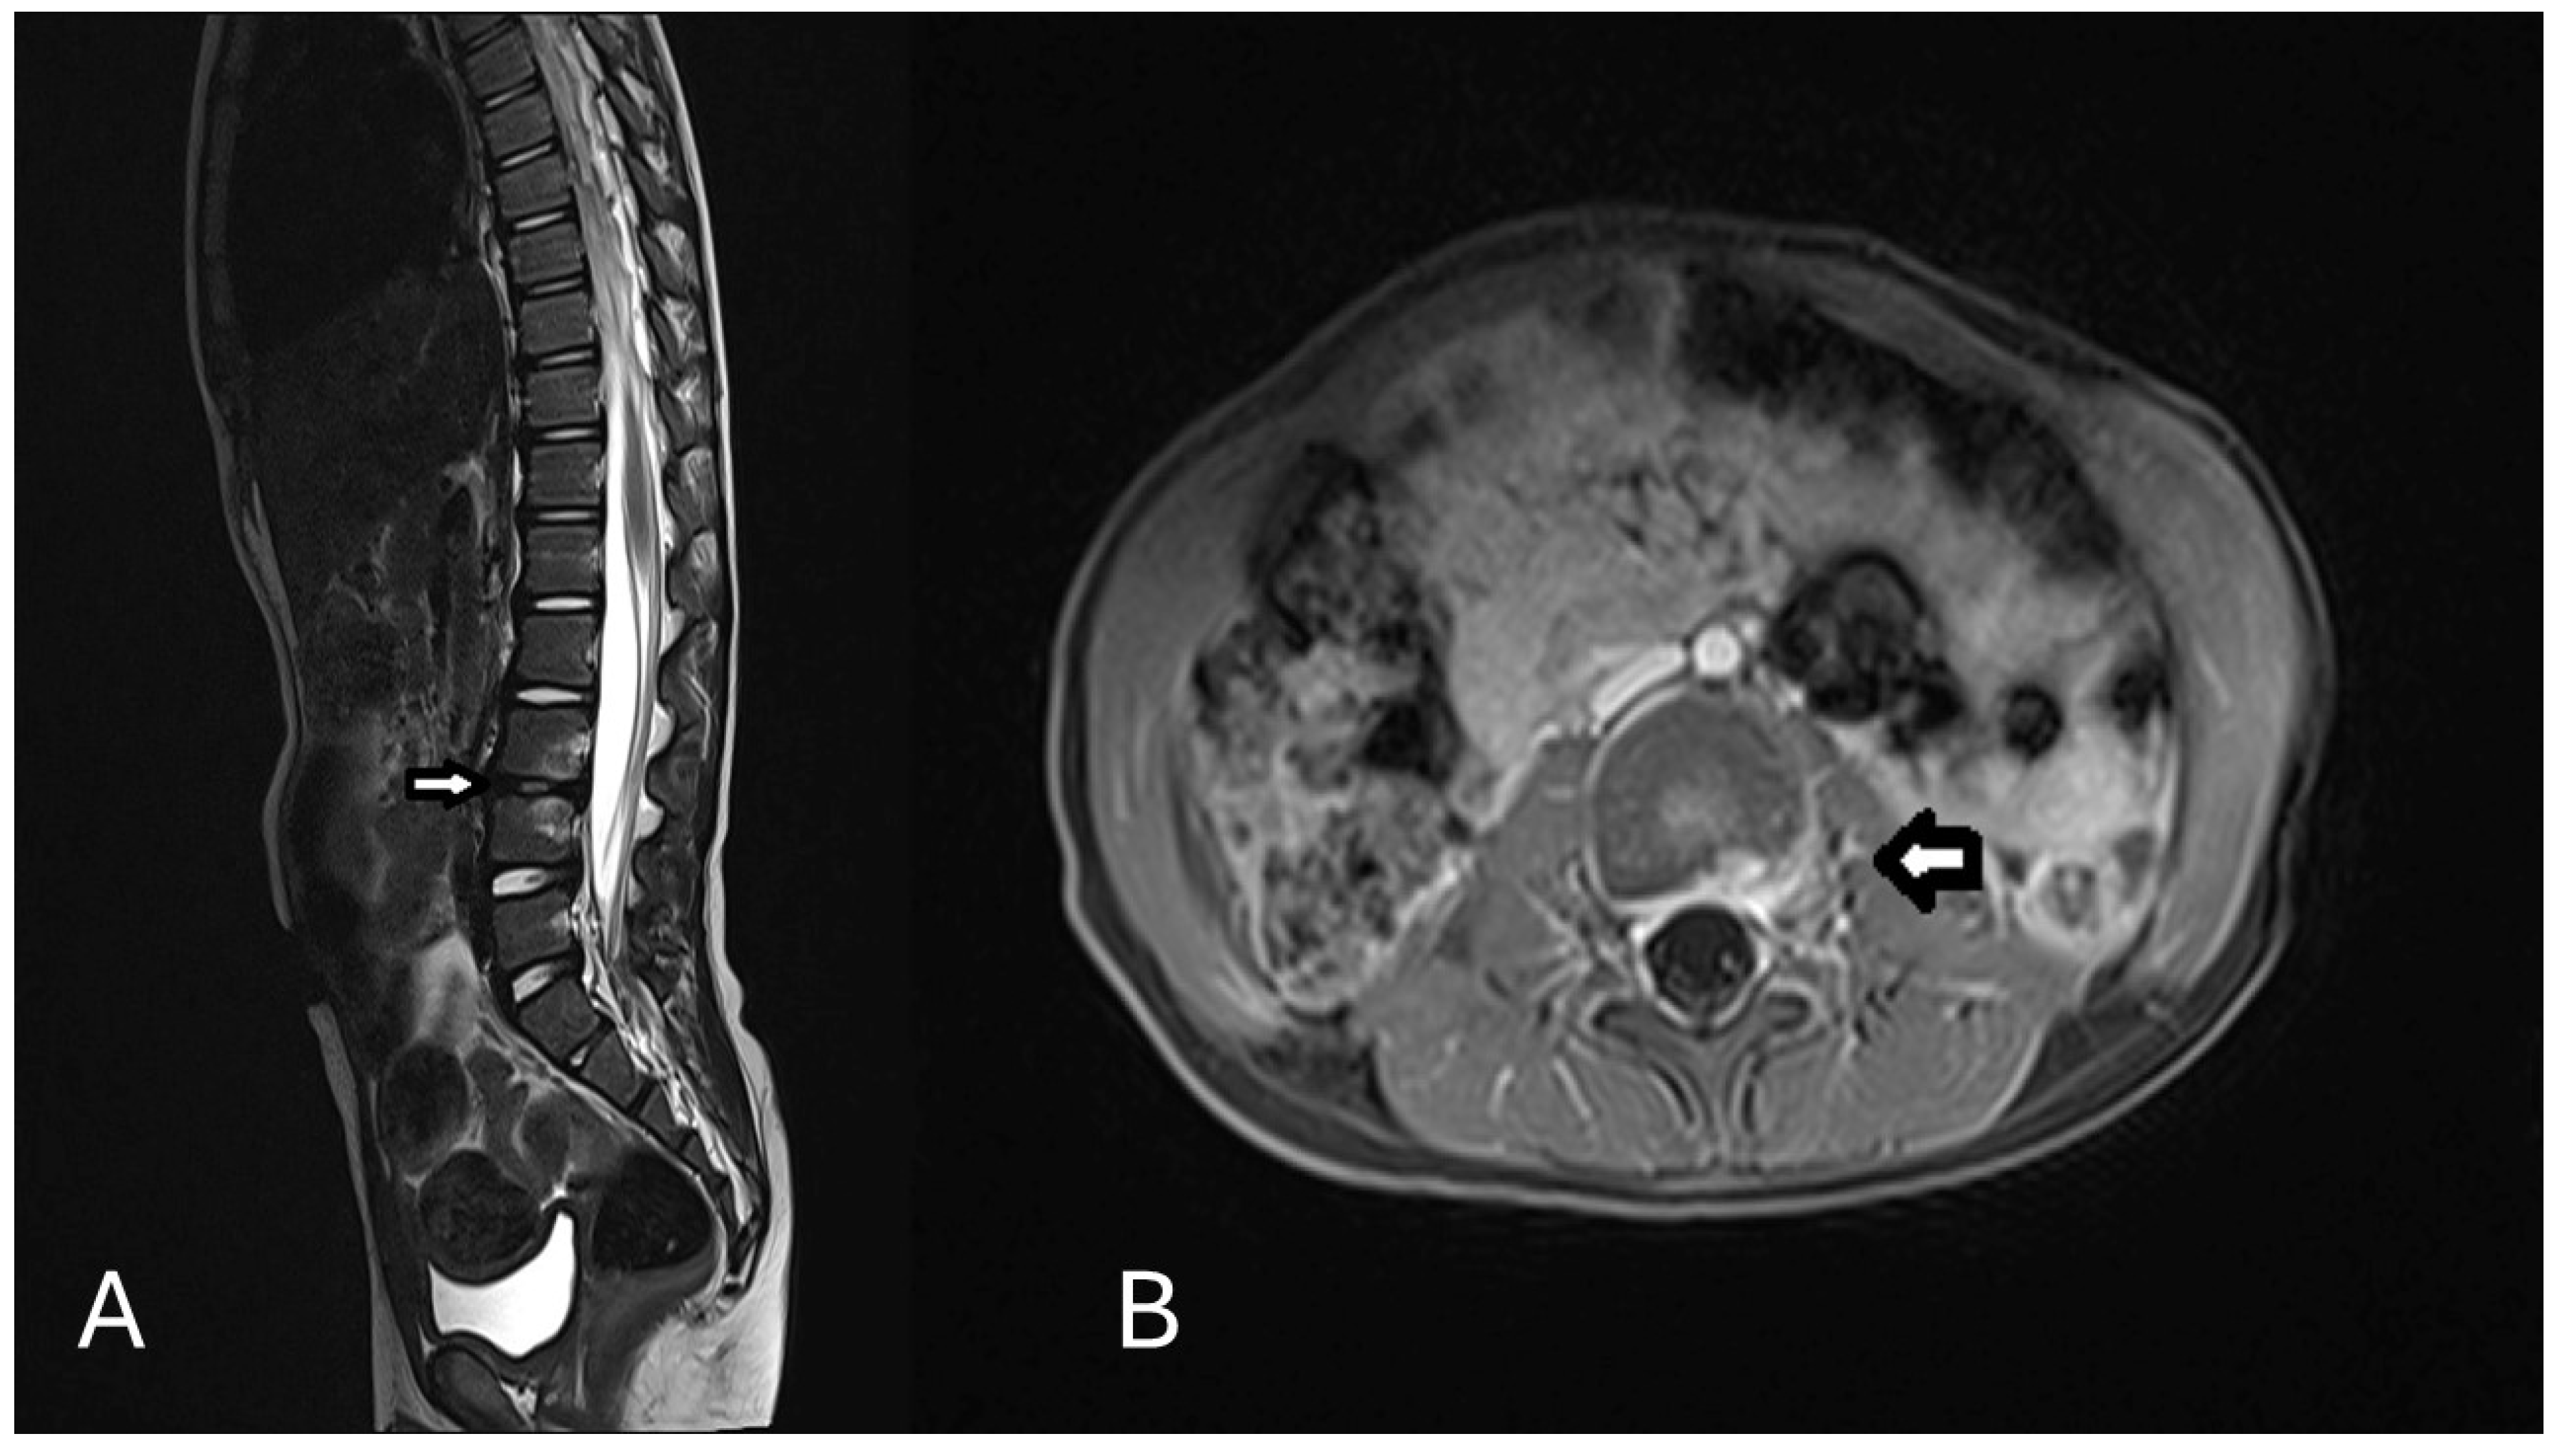

2. Case Presentation